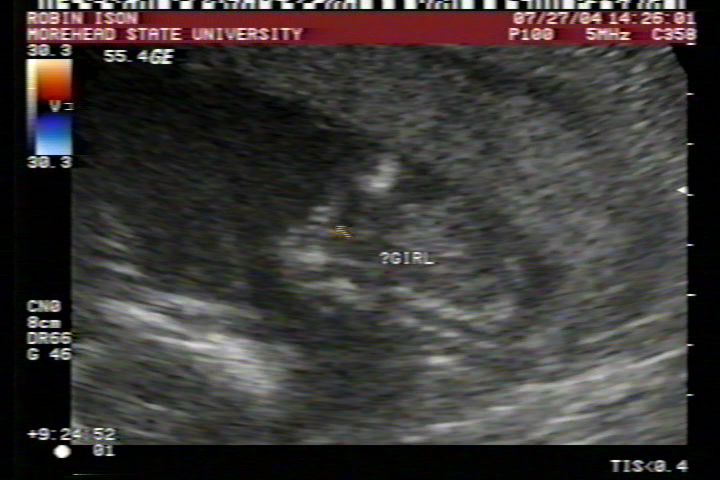

Pictures from Ultrasound at 17 weeks.